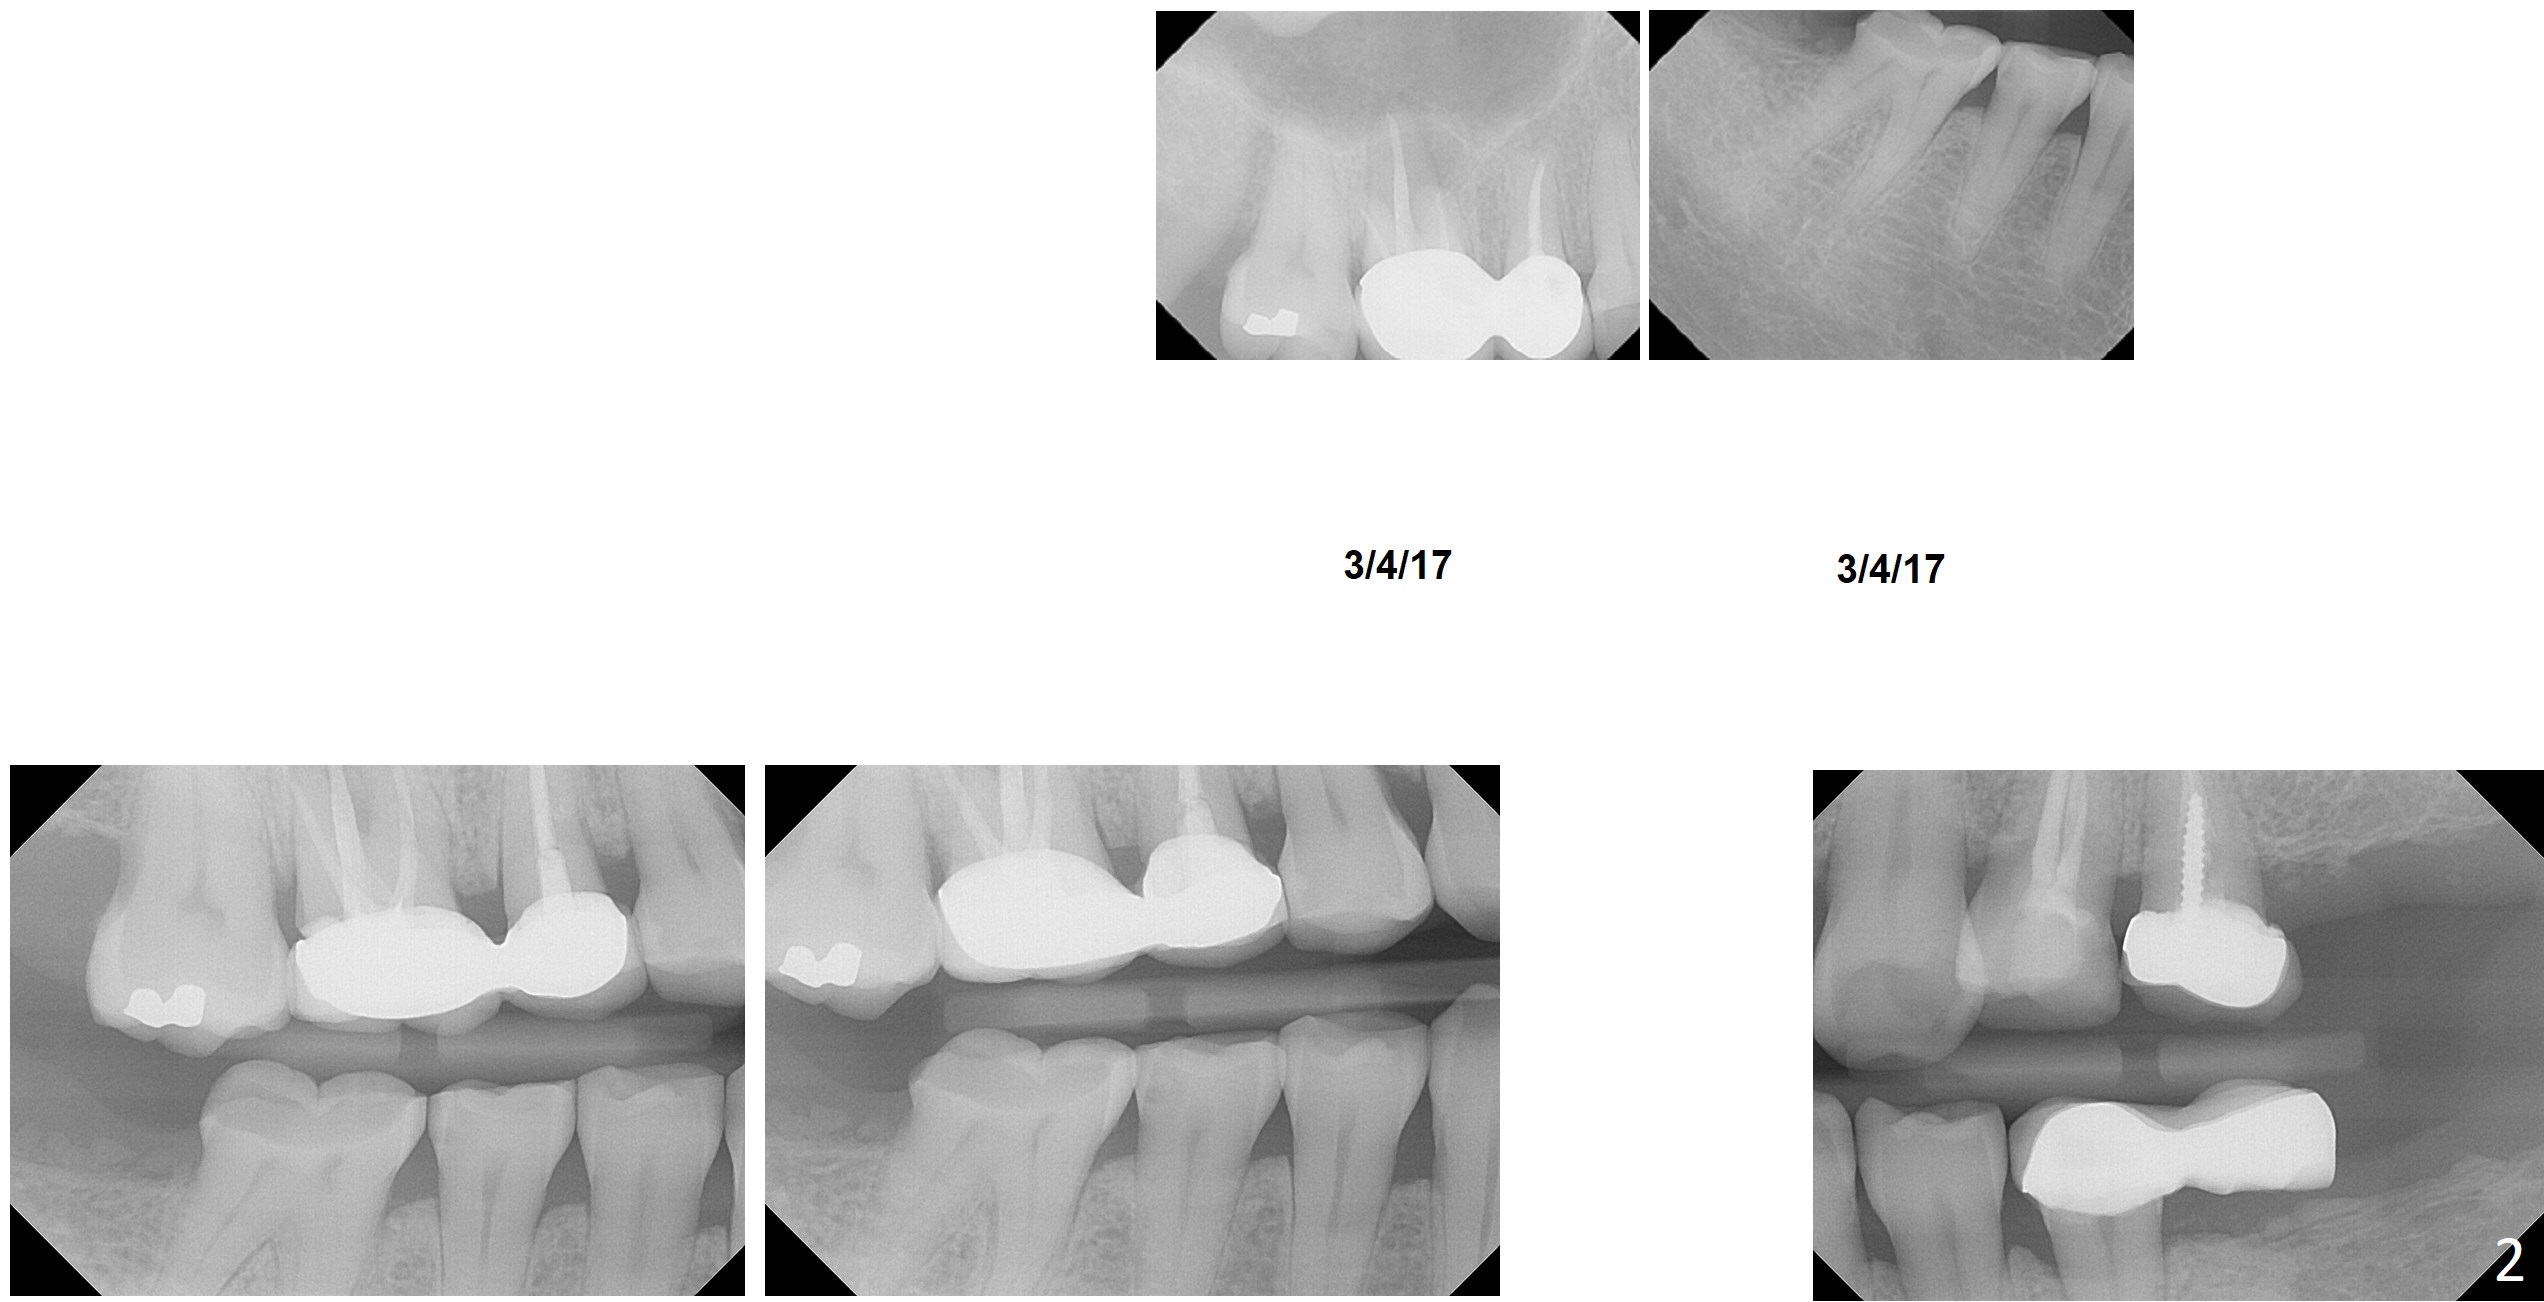

A 50-year-old healthy woman is determined to have implant placement at #14, 19 and 31 because of severe wear at #30. Crown will be fabricated at #30 first. The lower left cantilever bridge will be sectioned prior to CT and impression for scanning. Which implant should be placed first?